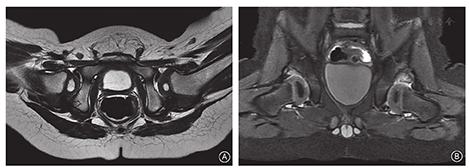

牵引石膏组入院后先行10~14 d双下肢垂直(屈髋90°)悬吊牵引,根据牵引后肌肉放松情况逐渐增加外展、屈髋角度(增加至110°)(图1)。牵引外展达60°以上时于手术室在吸入麻醉下行闭合复位及人类位石膏裤固定(图2)。术中评估外展< 60°不能维持复位或安全区(髋关节最大外展角度和股骨头复位后逐渐内收再次脱出时的外展角度之差)<20°时,放弃石膏裤固定。石膏裤固定术后行MR检查评估复位是否成功(图3)。石膏裤固定位置满足屈髋约110°、外展<60°,固定时间为患儿月龄(如患儿3月龄则石膏固定3个月),6周~2个月后根据石膏裤松紧更换二期石膏裤。牵引石膏治疗复位失败的患儿行切开复位手术治疗。